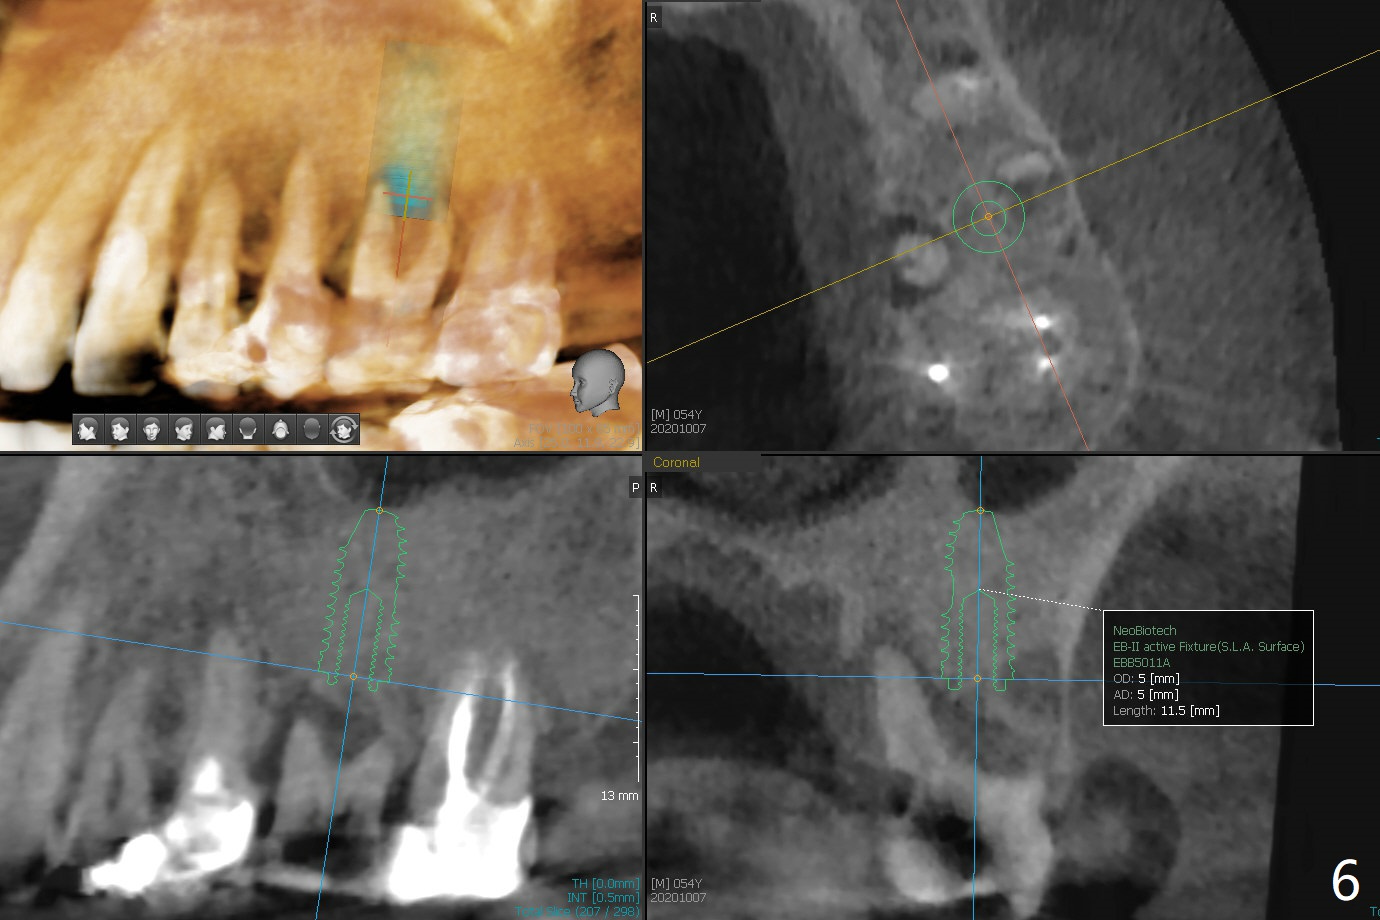

54岁男牙齿问题好像与牙周病和咀嚼力大有关(图一),虽然右上3(图二)和左下6(图三,四)需要治疗,因为疼痛他要求先处理左上6(图五)。后者腭侧根骨质吸收严重,植体尽量颊侧植入(图六),4.5 或者5.0x11毫米。放置粘性骨粉至植体平台,为了简化术中基台放置,使用Non-Hex Temporary Abutment,临时牙冠做的尽量大,占据牙槽窝空间,最后将PRF膜塞入两者之间。Return to Prevent Molar Periimplantitis (Protocols, Table) No Deviation No Caries Metronidazole CT/前牙植牙 Socket Shield Xin Wei, DDS, PhD, MS 1st edition 10/11/2020, last revision 02/21/2021